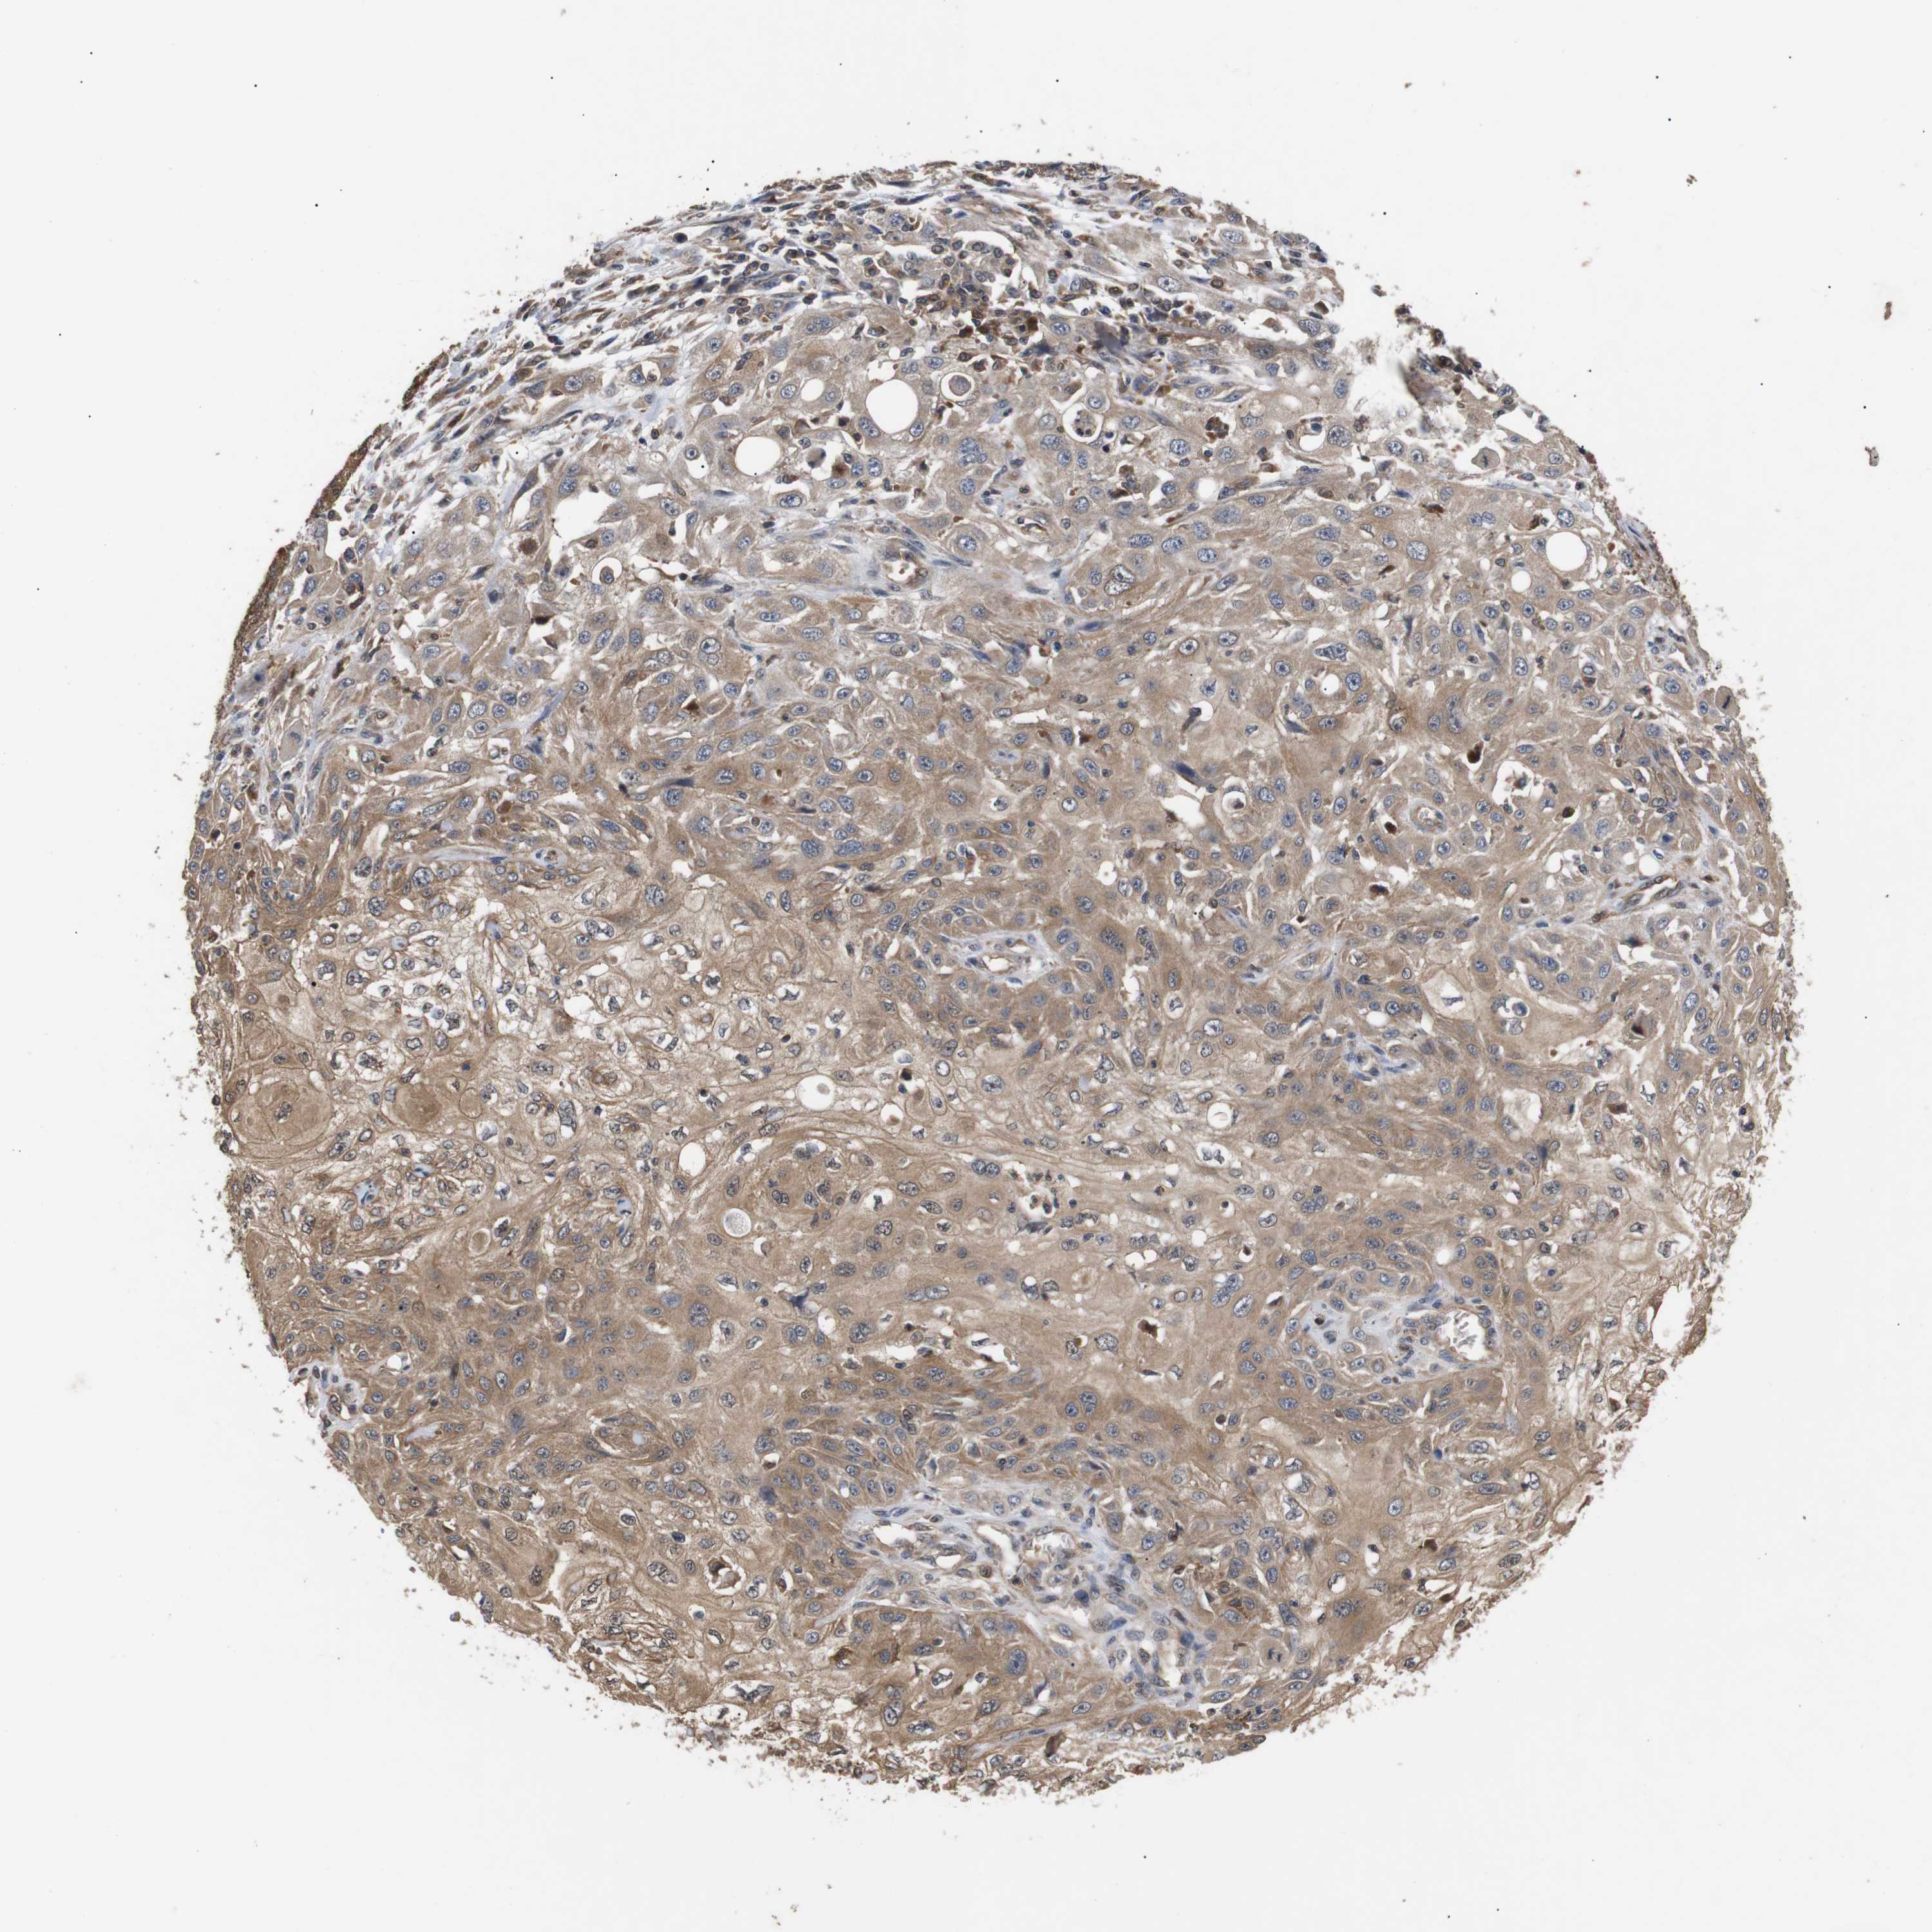

SKIN CANCER - Protein expressioni

A mouse-over function shows sample information and annotation data. Click on an image to view it in a full screen mode. Samples can be filtered based on level of antibody staining by selecting one or several of the following categories: high, medium, low and not detected. The assay and annotation is described here.

Antibody stainingi

Antibody staining in the annotated cell types in the current human tissue is reported as not detected, low, medium, or high, based on conventional immunohistochemistry profiling in selected tissues. This score is based on the combination of the staining intensity and fraction of stained cells.

Each image is clickable and will lead to virtual microscopy that enables deeper exploration of all samples and also displays staining intensity scores, fraction scores and subcellular localization as well as patient and tissue information for each sample.

Antibody CAB010162

Antibody CAB025656

Staining

High

Medium

Low

Not detected

Intensity

Strong

Moderate

Weak

Negative

Quantity

>75%

75%-25%

<25%

None

Location

Nuclear

Cytoplasmic/membranous

Cytoplasmic/membranous,nuclear

Squamous cell carcinoma, NOS

Basal cell carcinoma

Squamous cell carcinoma, metastatic, NOS